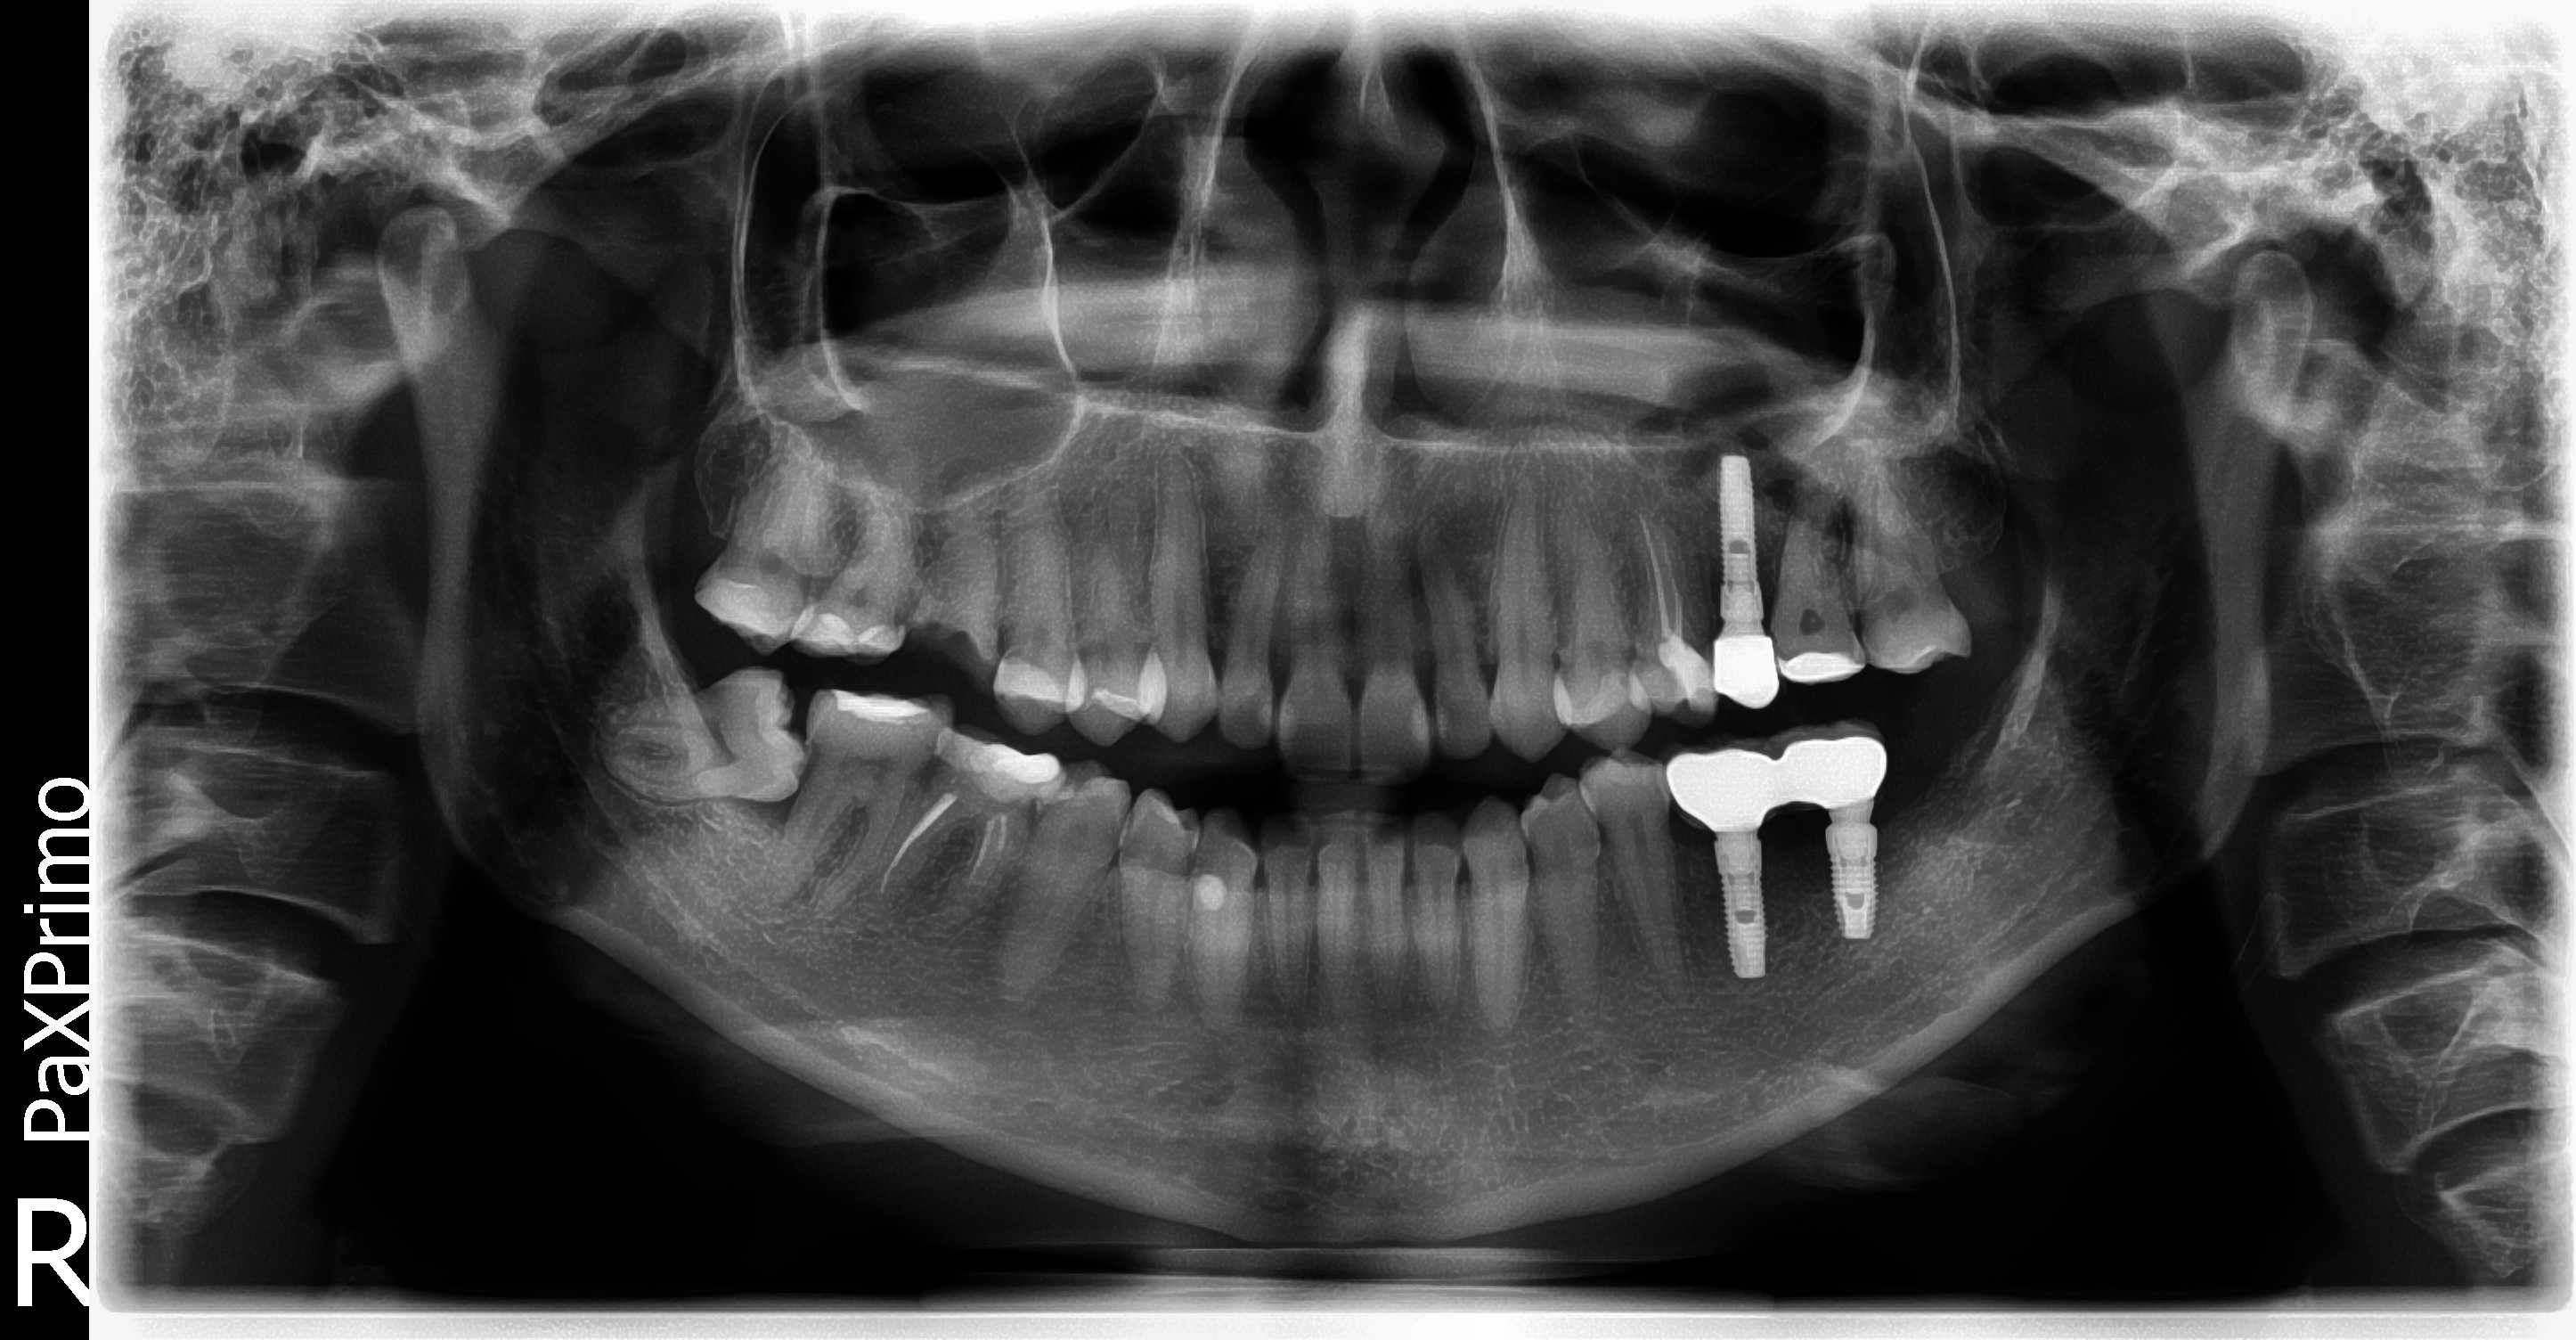

Исследование на рентгене после имплантации зубов

Раздел: Снимки-откровения